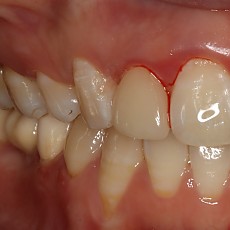

시술전후사진 8 페이지

Total 189건 8 페이지